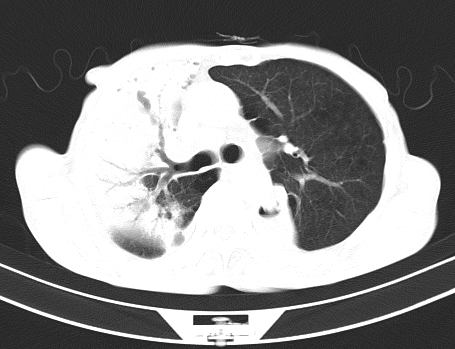

以下是引用gaoshengjiang在2008-5-30 19:53:00的发言:[br]右上叶可见大片实变影,其内可见充气支气管影及囊状影,右上叶尖端支气管走形区可见结节样影,左侧胸腔内可见胸腔胃影。纵隔淋巴结肿大。[br]考虑:1.右上肺阻塞性肺炎伴肺脓肿形成。支持转移所致。[br] 2.左侧胸腔胃。